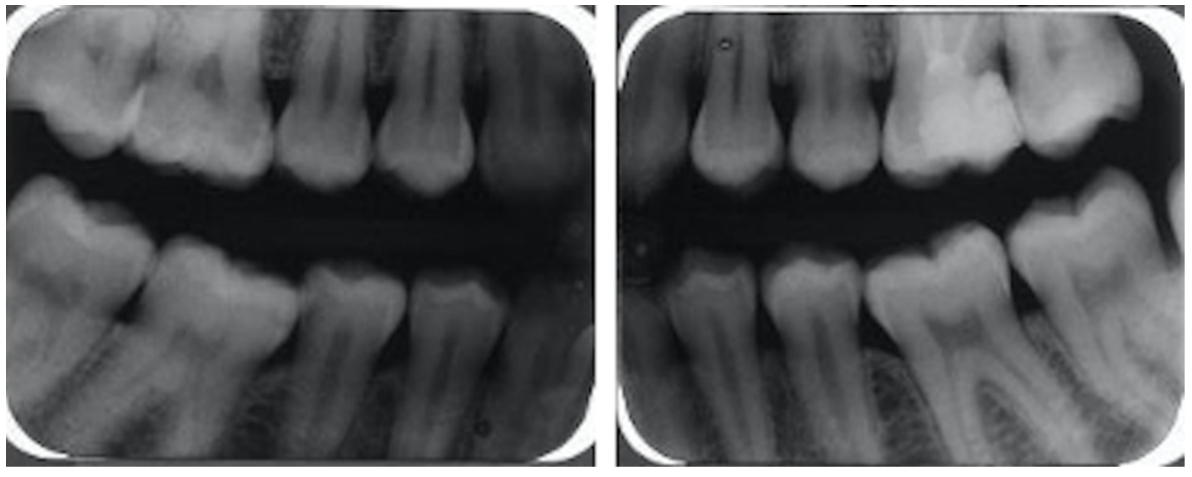

2.3. Oral Examination